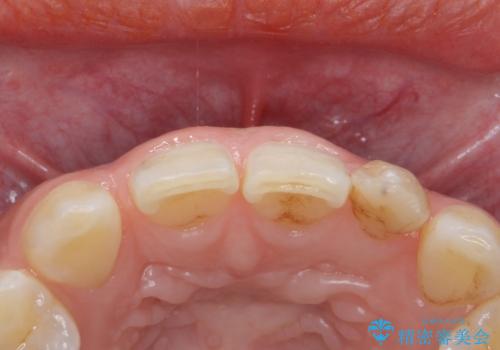

- 左上の前歯の変色が気になるとのことで来院されました。

もともと小さい歯(矮小歯)に樹脂が盛り足されている状態でした。

今後の変色をなくすために樹脂ではなくセラミックでの治療を行います。

セラミックでの治療をすることにより今後の変色を抑えることができます。

色・形ともに改善することができ大変喜んでいただけました。